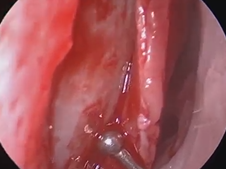

Microdirect Laryngoscopy and CO2 Laser Total Vestibulectomy for Pyolaryngocele

- Date : 01/01/2020

Microdirect Laryngoscopy with CO2 Laser Wedge Excisions for Subglottic Stenosis